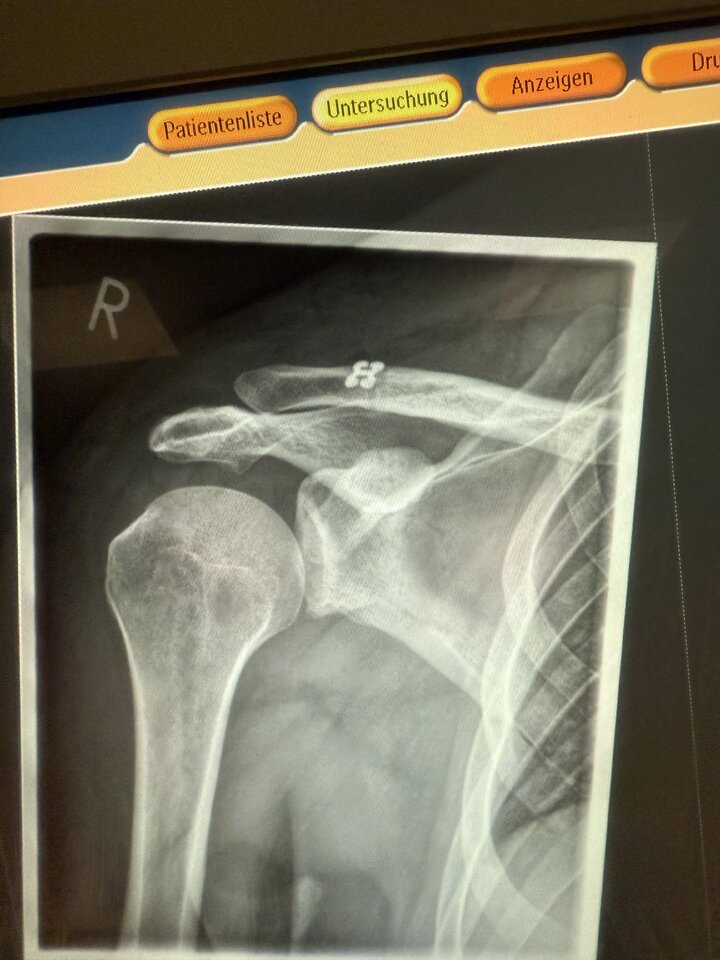

Ja, lieber Arm dran als Arm ab.Alles wieder schick in meiner Schulter

Alles wieder schick in meiner Schulter

Aber die Schmerzen sind heftig - leider immer noch.... Bekomme nahezu im 2 Stunden Rhythmus Ibu/Novalgin/Oxy....

Heute soll Oxy auf Tilidin runtergestuft werden, ich hoffe, dass wird langsam mal besser

Doc sagt in 3 Monaten können wir uns über Bass spielen unterhalten, je nachdem wie gut Physio funktioniert![]()